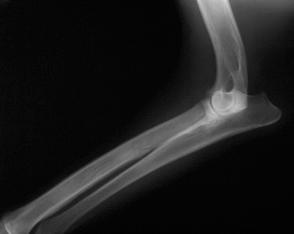

Figura 3.Câine. Radiografie membrul anterior stâng, regiunea antebrațului, incidență latero-laterală. Semne de neomogenitate a matricei osoase (radius), aspect de fum de țigară – panosteită. Radiografie în sistem digital